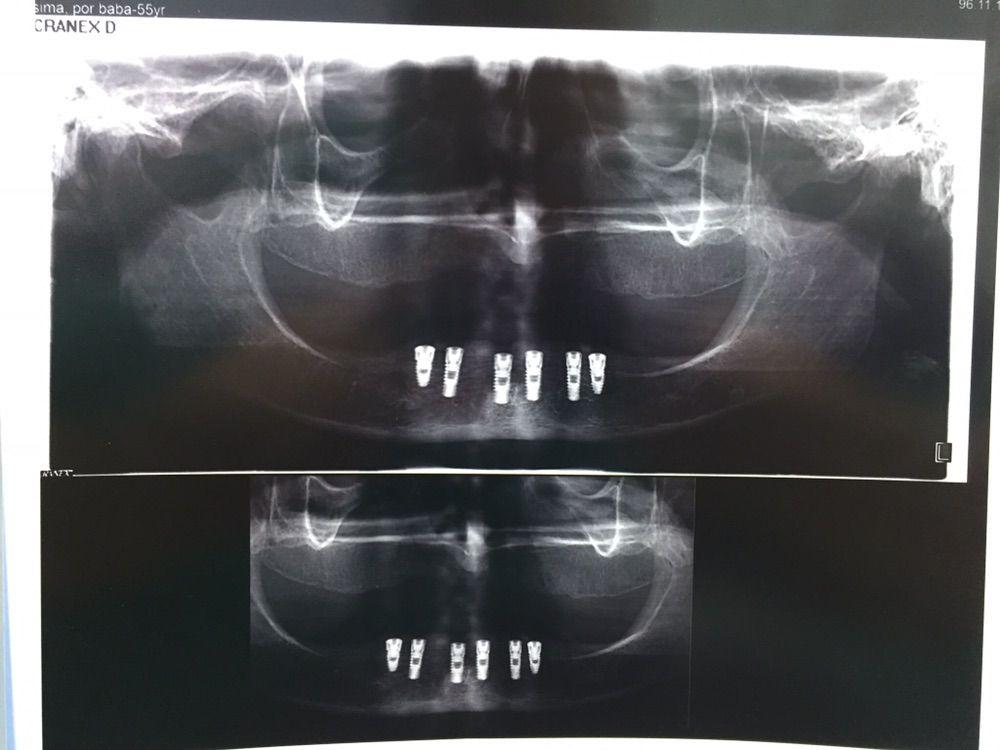

– جراحی های پیشرفته ایمپلنت دندان

جراحی ایمپلنت دندان و گذاشتن پروتز در ناحیه فک و صورت